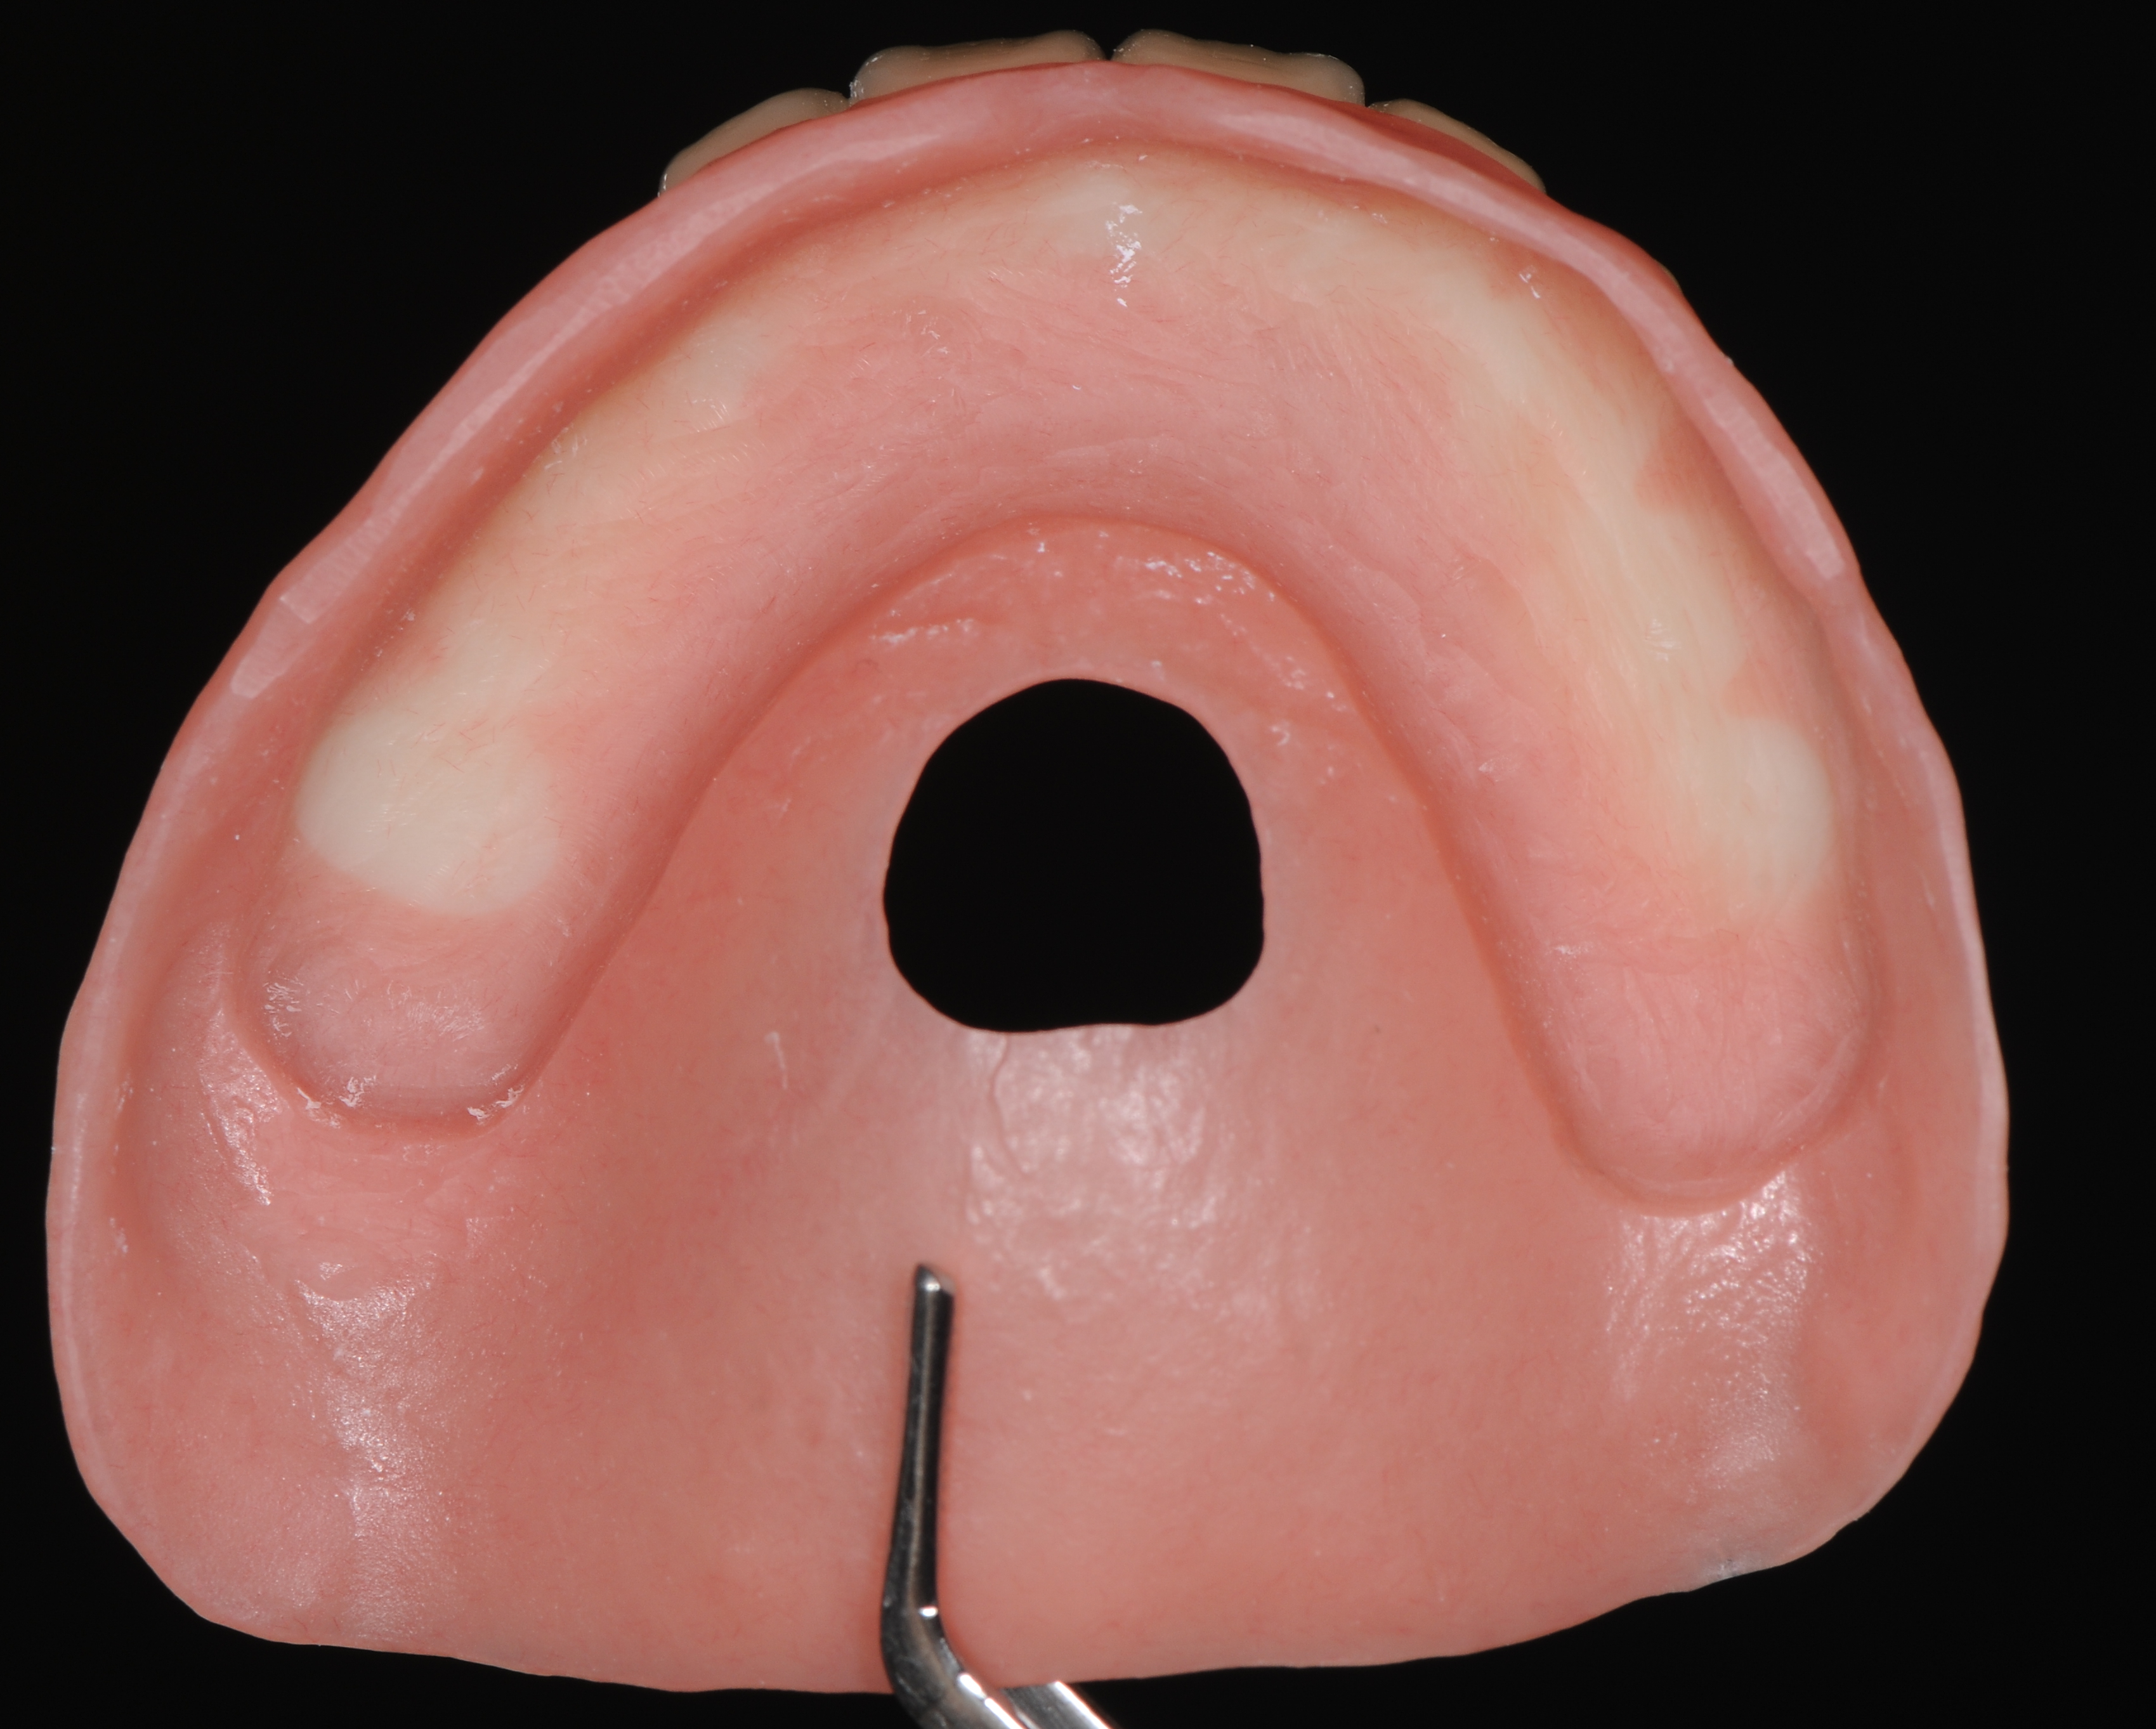

Перед проведением хирургического вмешательства были выполнены все этапы цифровой диагностики и планирования будущей работы. Изготовлены хирургический шаблон и акриловый базис будущего протеза, с ложем для последующего армирования (упрочнения) и индивидуализации временного протеза в день установки имплантатов на верхней челюсти. (рис. 5,6,7,8)

Хирургическое вмешательство проводилось в состояние медикаментозной седации в комбинации с местной анестезией. С использованием хирургического навигационного шаблона, пилотной фрезой была проведена разметка положения имплантатов на верхней челюсти. На начальном этапе без откидывания лоскутов. В боковых участках разрез десны проводился по вершине альвеолярного гребня, во фронтальном отделе выбран вестибулярный разрез с отступом около 2-3 мм от границы соединения прикреплённой десны к слизистой оболочки переходной складки для дальнейшего управляемого формирования зоны кератинизированной десны в области имплантатов. (рис 8,9,10)